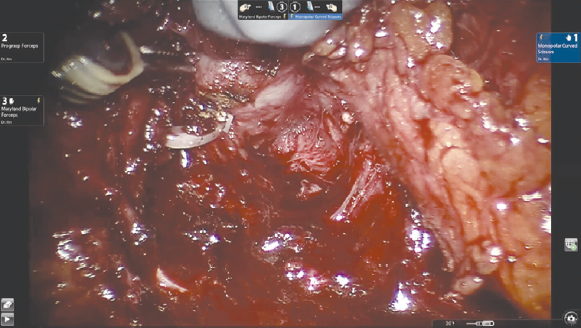

Вскрытие париетальной брюшины в проекции шейки мочевого пузыря. Операция выполняется трансперитонеально, расположение роботических троакаров повторяет таковое при традиционном доступе. Ассистентские 12- или 5-миллиметровые порты также устанавливаются стандартно: параректально справа на 2–3 см выше оптического порта и на 6–8 см латерально от правого роботического порта соответственно. На первом этапе происходит вскрытие париетальной брюшины. В отличие от традиционного доступа, инцизия производится в проекции шейки мочевого пузыря, а не его верхушки. Для лучшей визуализации третьим роботическим инструментом осуществляется тракция задней стенки мочевого пузыря вверх. Выделение семявыносящих протоков и семенных пузырьков (рис. 1). Этот этап операции выполняется сразу после вскрытия париетальной брюшины. Техника диссекции семявыносящих протоков и семенных пузырьков не отличается от стандартной. Основным фактором, обеспечивающим техническую сложность этого этапа, является небольшой объем операционного поля и невозможность выполнения широких тракций семенных пузырьков и самой предстательной железы, которая на данном этапе остается выделенной лишь на небольшой поверхности ее основания. Выделение задней поверхности простаты и сосудисто-нервных пучков (рис. 2), как и при традиционном доступе, происходит после этапа выделения семенных пузырьков. Уровень нервосбережения определяется на основании стадии опухолевого процесса. Для доступа к заднелатеральным отделам предстательной железы выполняется частичная латеральная диссекция пузырно-простатических мышечных волокон. Диссекция шейки мочевого пузыря (рис. 3) выполняется в направлении снизу вверх и является одним из самых сложных шагов этой операции. На этом этапе в наибольшей степени проявляется преимущество свободно изгибающихся на концах роботических инструментов. Для лучшей визуализации используется развернутая наверх (30°) оптика. Шейка мочевого пузыря вскрывается по задней поверхности, уретральный катетер извлекается, после чего рассекается передняя ее поверхность. Диссекция дорзального сосудистого комплекса производится тупым и острым путем без предварительного прошивания и перевязывания. После выделения верхушки простаты железа отсекается от уретры. На этом этапе при необходимости производится прошивание элементов дорзального комплекса. На рис. 4 представлено ложе удаленной предстательной железы. Наложение пузырно-уретрального анастомоза (рис. 5) начинается с передней его стенки на 12 ч условного циферблата. Анастомоз выполняется с использованием самозатягивающихся нитей. Сложность этого этапа обусловлена, в основном, непривычной визуализацией. Ввиду того, что мобилизация мочевого пузыря не производилась, сопоставление слизистой уретры и мочевого пузыря происходит без видимого натяжения, поэтому усиления соустья с помощью дополнительной реконструкции не требуется. При необходимости выполняется задняя пластика шейки мочевого пузыря. Последним этапом производится установка дренажа к зоне анастомоза и ушивание париетальной брюшины.

Рис. 1. Выделение семявыносящих протоков и семенных пузырьков

Fig. 1. Isolation of the vas deferens and seminal vesicles